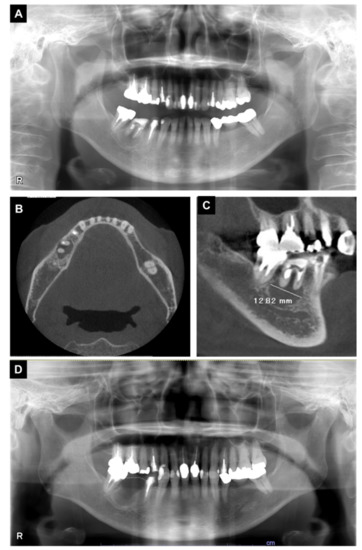

3. Case Report